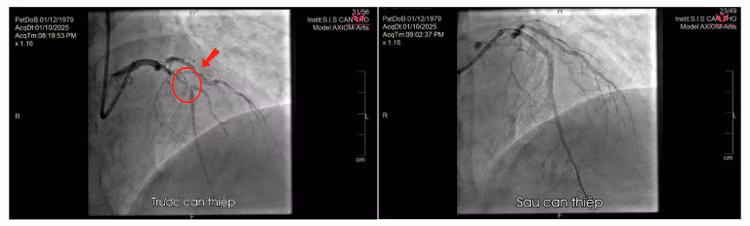

Kết quả chụp mạch vành cấp cứu ghi nhận tắc đoạn gần nhánh liên thất trước. Hình ảnh trước – sau can thiệp - Ảnh BVCC

Ê-kíp tim mạch khẩn trương hội chẩn và chỉ định chụp mạch vành cấp cứu, phát hiện tổn thương hẹp rất nặng ở đoạn gần nhánh liên thất trước. Bệnh nhân được đặt stent mạch vành cấp cứu để tái thông dòng máu.